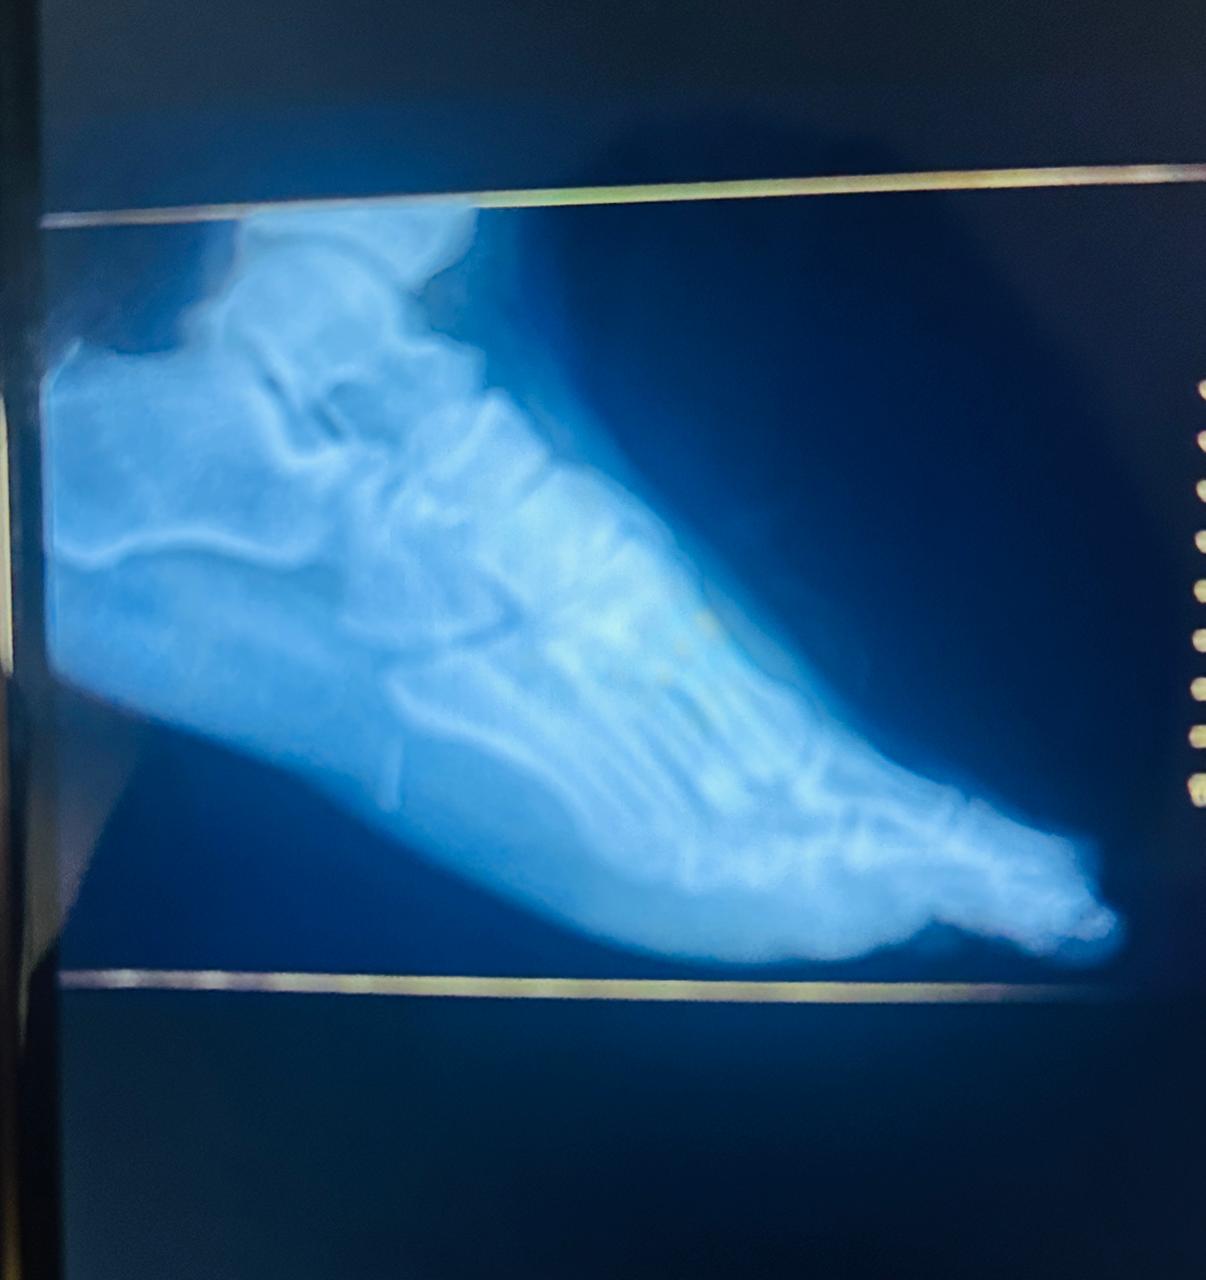

Um homem de 46 anos precisou passar por cirurgia após sofrer um acidente com um peixe em Maceió. Lucas Ferreira Galdino estava pescando com a família quando pisou em um bagre. O ferrão do animal quebrou e ficou alojado profundamente no pé direito, causando dor intensa.

Inicialmente, ele foi levado para uma Unidade de Pronto Atendimento (UPA), mas, devido à profundidade do ferimento, não foi possível retirar o ferrão. Em seguida, foi encaminhado ao Hospital Regional de Palmeira dos Índios (HRPI), onde passou por cirurgia.

O procedimento foi realizado pela equipe médica do hospital, sob coordenação do cirurgião geral Rafael Pinheiro, que conseguiu retirar o ferrão em fragmentos, sem deixar resíduos. Segundo o médico, o paciente recebeu alta com orientações de repouso e uso de medicação.